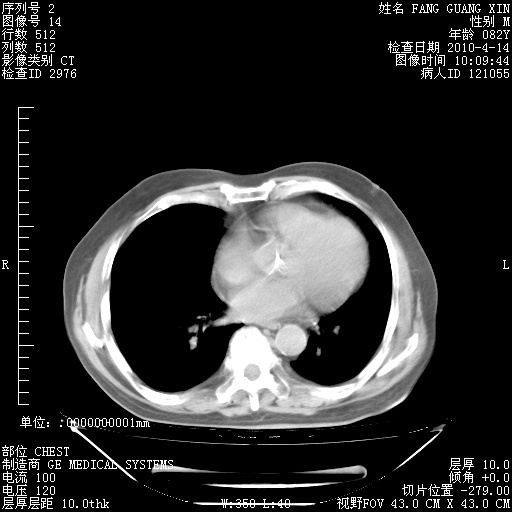

4月14日肺部CT

23.JPG

24.JPG

25.JPG

26.JPG

肺部CT平扫未见异常。